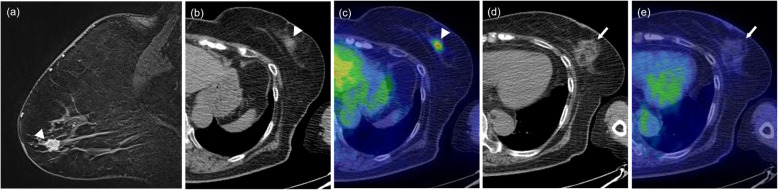

Fig. 3.

Fatty mass type. A 74-year-old woman with invasive ductal carcinoma. Breast MRI before cryoablation (a, arrowhead) showing a solid nodule of diameter 11 mm in the outer-lower quadrant of the left breast. The pre-cryoablation CT portion (b, arrowhead) and fusion image (c, arrowhead) of PET/CT show a solid nodule with abnormal FDG uptake (SUVmax, 3.53). On the CT portion (d, arrow) and (e, arrow) fusion image of PET/CT that was obtained 11 months after cryoablation, the treated area shows a focal fatty area and septa of soft tissue density with subtle FDG uptake (SUVmax, 1.34)